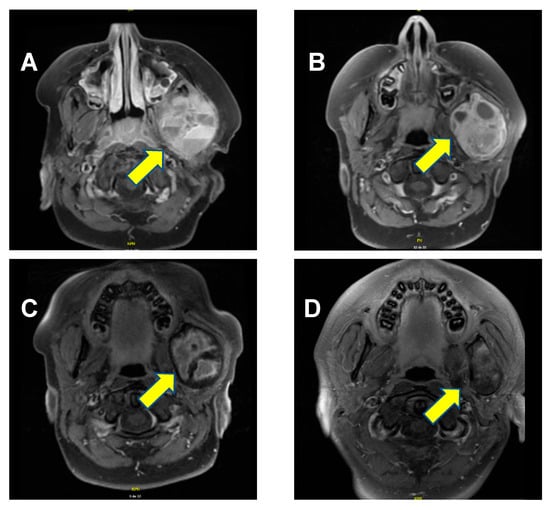

A previously healthy 9-year-old boy presented with worsening edema of the left cheek that had developed over the course of several months. The patient had a visible and palpable lesion on the left branch of the jaw, which was mildly tender upon pressure. The mass was firm, and there was erythema. Of note, there were no other significant symptoms such as swallowing difficulties or difficulty breathing or speaking. The patient’s past medical history was entirely unremarkable. Notably, there was no evidence of intrauterine growth restriction or prematurity, and there were no clinical signs or family history of rickets. A cervical magnetic resonance imaging (MRI) confirmed the presence of a lesion measuring 5.2 cm × 4.6 cm × 4.1 cm located on the ascending branch of the left mandible, including the mandibular condyle. It presented several cystic components, measuring up to 4 cm× 2.6 cm. The masseter, temporal, and pterygoid musculature were lightly infiltrated by the lesion (Figure 1A). A temporomandibular biopsy was performed. The histopathology analysis showed bone and fibrous hemorrhagic fragments with evidence of fusiform mononuclear cells, as well as several multinuclear osteoclast-like cells, confirming the diagnosis of an aneurysmal bone cyst.

Figure 1. Axial T1-weighted MRI scan with gadolinium. (A) At diagnosis, a lesion of 5.2 cm × 4.6 cm × 4.1 cm was evidenced (arrow), containing multiple cystic components, with the bony cortex hard to establish and a relatively central enhancement. (B) Three months following the initiation of denosumab, the lesion measured 5.3 cm × 4.4 cm × 3.7 cm. The cystic components had diminished in size, enhancement appeared more important since the cystic parts were diminished, but the intensity of enhancement was similar. (C) About a month after administration of the last dose, the lesion measured 5.1 cm × 4.1 cm × 3.6 cm. Internal enhancement foci were still present, especially in the periphery. (D) Twenty-six months after treatment discontinuation, the lesion measured 4.3 cm × 2.6 cm × 3.5 cm. Post-contrast enhancement of signal anomalies was diminished on T2-weighting, showing that the radiological shrinkage of the lesion persisted.

Denosumab 2 mg/kg (120 mg) was administered subcutaneously once weekly for the first four weeks, then 2 mg/kg (120 mg) once a month for the subsequent sixteen months. This dose was selected based on previous experiences reported in the literature [,,]. Supplementation therapy of calcium and vitamin D was given daily during the treatment to prevent hypocalcemia. Clinical response was rapid, with lesion pain resolution within a month. There was also a progressive decrease in the lesion’s dimensions after 17 months of treatment (Figure 1C).

Remarkably, the lesion continued to shrink even after denosumab discontinuation. At the most recent follow-up MRI, performed 26 months after treatment discontinuation, the lesion measured 4.3 cm × 2.6 cm × 3.5 cm, (Figure 1D). Most importantly, the significantly deformed malformation on the left aspect of the mandible is clinically no longer apparent; the aneurysmal bone cyst is meanwhile just barely palpable, and the patient no longer complains of any pain. A timeline of the patient’s clinical course, from initial discovery to lesion regression and symptom resolution, is provided in Figure 2.

From a therapeutic perspective, our patient exhibited an excellent response to denosumab, with persisting ongoing reduction in the mass 26 months after treatment discontinuation (Figure 1D). The fact that this initial deforming lesion is no longer clinically noticeable has had a significant impact on this child’s self-esteem and quality of life. Of course, close clinical monitoring and follow-up remain essential, as there are reports of tumor recurrence after denosumab discontinuation [,].